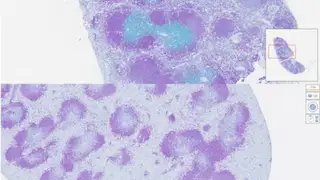

Estas partículas microscópicas están fabricadas con polímeros que se degradan en agua y llevan en su interior ARN mensajero (mRNA), el mismo tipo de molécula utilizada en algunas vacunas modernas. Ese material genético contiene instrucciones para que las células T fabriquen receptores capaces de detectar y destruir células B, un tipo de célula inmunitaria implicada en enfermedades como el lupus y en cánceres como la leucemia o el linfoma.

Para encontrar su objetivo, la superficie de las nanopartículas está decorada con dos moléculas de anticuerpo (antiCD3 y antiCD28) que actúan como una especie de sistema de guiado. Estas proteínas permiten que las partículas se adhieran específicamente a las células T y las activen. Una vez dentro, las nanopartículas se degradan y liberan su carga genética, reprogramando a las células inmunitarias desde el interior. El proceso se asemeja, según el estudio, al lanzamiento de un cohete.

Aun así, el equipo logró mejorar notablemente la eficiencia del proceso: alrededor de un 10% de sus nanopartículas conseguían liberar su carga genética, frente al 1% o 2% típico de otras tecnologías similares. Las pruebas en ratones mostraron que, veinticuatro horas después de una sola inyección, el 95% de las células B circulantes en la sangre había desaparecido, mientras que aproximadamente la mitad de las células B del bazo también habían sido eliminadas.